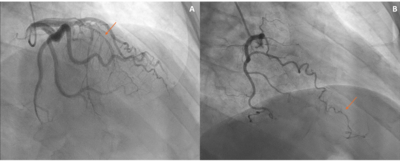

A 60-year-old male with no prior medical history presented with lightheadedness and stable exertional chest pain. Vital signs and physical examination were unremarkable. Electrocardiogram showed normal sinus rhythm with an old inferior and anteroseptal infarction. Echocardiography revealed normal EF with no clear wall motion abnormalities. A myocardial perfusion stress test showed moderate fixed reduced radiotracer uptake with mild reversibility at the LAD territory (Figure 1). Coronary computed tomography angiography revealed a calcified and non-calcified plaque in the proximal to mid LAD with apical LVT (Figure 2[A-B]). Left heart catheterization showed a total mid LAD occlusion with collateral circulation from the acute marginal branch of the right coronary artery to distal LAD (Figure 3[A-B]). Further work-up revealed a JAK2 V617F mutation. The patient was treated with apixaban, atorvastatin, and metoprolol.